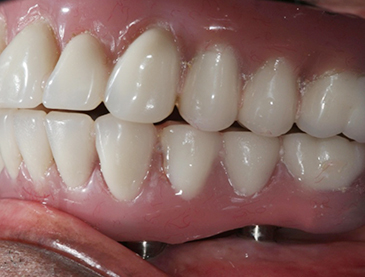

Implants/Bone Grafting

Fully edentulous clinical cases